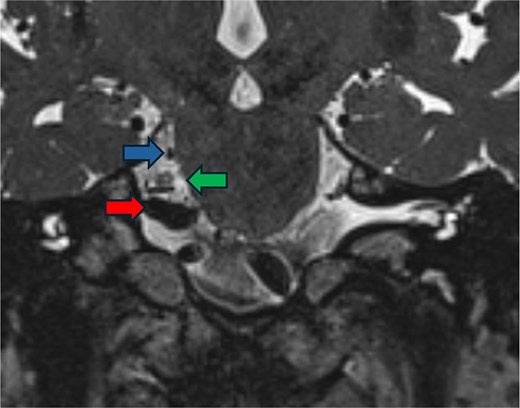

AR visualization of the 3D model demonstrated a laterally and superiorly deviated vertebrobasilar junction with a compressive dolichoectatic and atherosclerotic elbow of the right vertebral artery causing compression as it traversed underneath the trigeminal nerve root entry zone (Fig. 1). A downward-looping superior cerebellar artery was also compressing the nerve from above. In the operating room, the AR system was used to register the 3D model onto the patient’s head, which allowed us to plan the incision and craniotomy location in a more individualized manner and to optimally position the patient for a more ergonomic operation (Fig. 2 and Video 1). The AR overlay displayed the underlying transverse–sigmoid junction, allowing a more accurate burr hole placement. There was a loop of the superior cerebellar artery which was compressing the nerve superiorly at the root entry zone. The vertebral artery was identified. We created a sling with a 4-0 Nurolon suture wrapping around the vertebral artery and suturing it to the dura inferiorly (Video 2). Teflon pledgets were then used to pad the nerve and it was now completely decompressed from the vascular structures. Postoperative MRI of the brain showed effective decompression of the trigeminal nerve (Fig. 3).

Postoperative imaging. FIESTA scan demonstrating the relief of compression of the trigeminal nerve (green arrow) by the vertebral artery (red arrow) and the superior cerebellar artery (blue arrow).